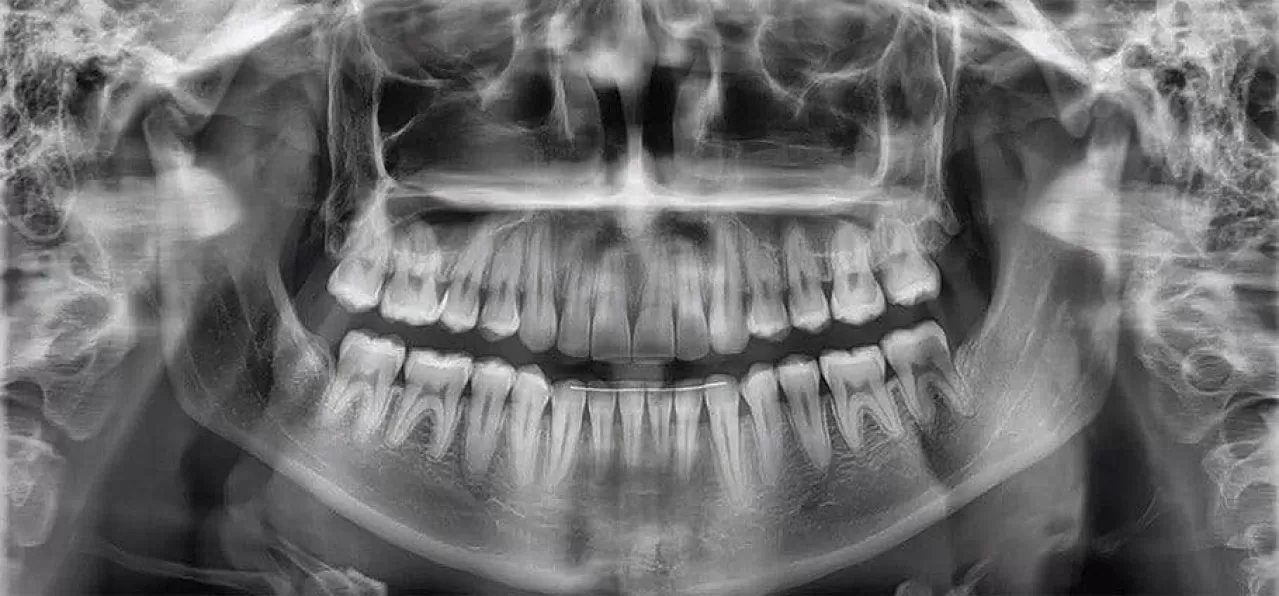

Zubni rendgen (tzv. 2D ortopan) je bitan korak pri određivanju odgovarajuće terapije i medicinskog zahvata.

Provodi se kako bi stomatolog dobio što bolji uvid u trenutačno oralno zdravlje i na taj način odredio ispravnu terapiju.

Digitalne rendgenske snimke zuba i čeljusti omogućuju detaljan uvid u anatomske osobitosti zuba, dijagnosticiranje patoloških procesa, stanje i debljinu kosti prije implantoloških zahvata kao i stupanj gubitka kosti uslijed parodontitisa.